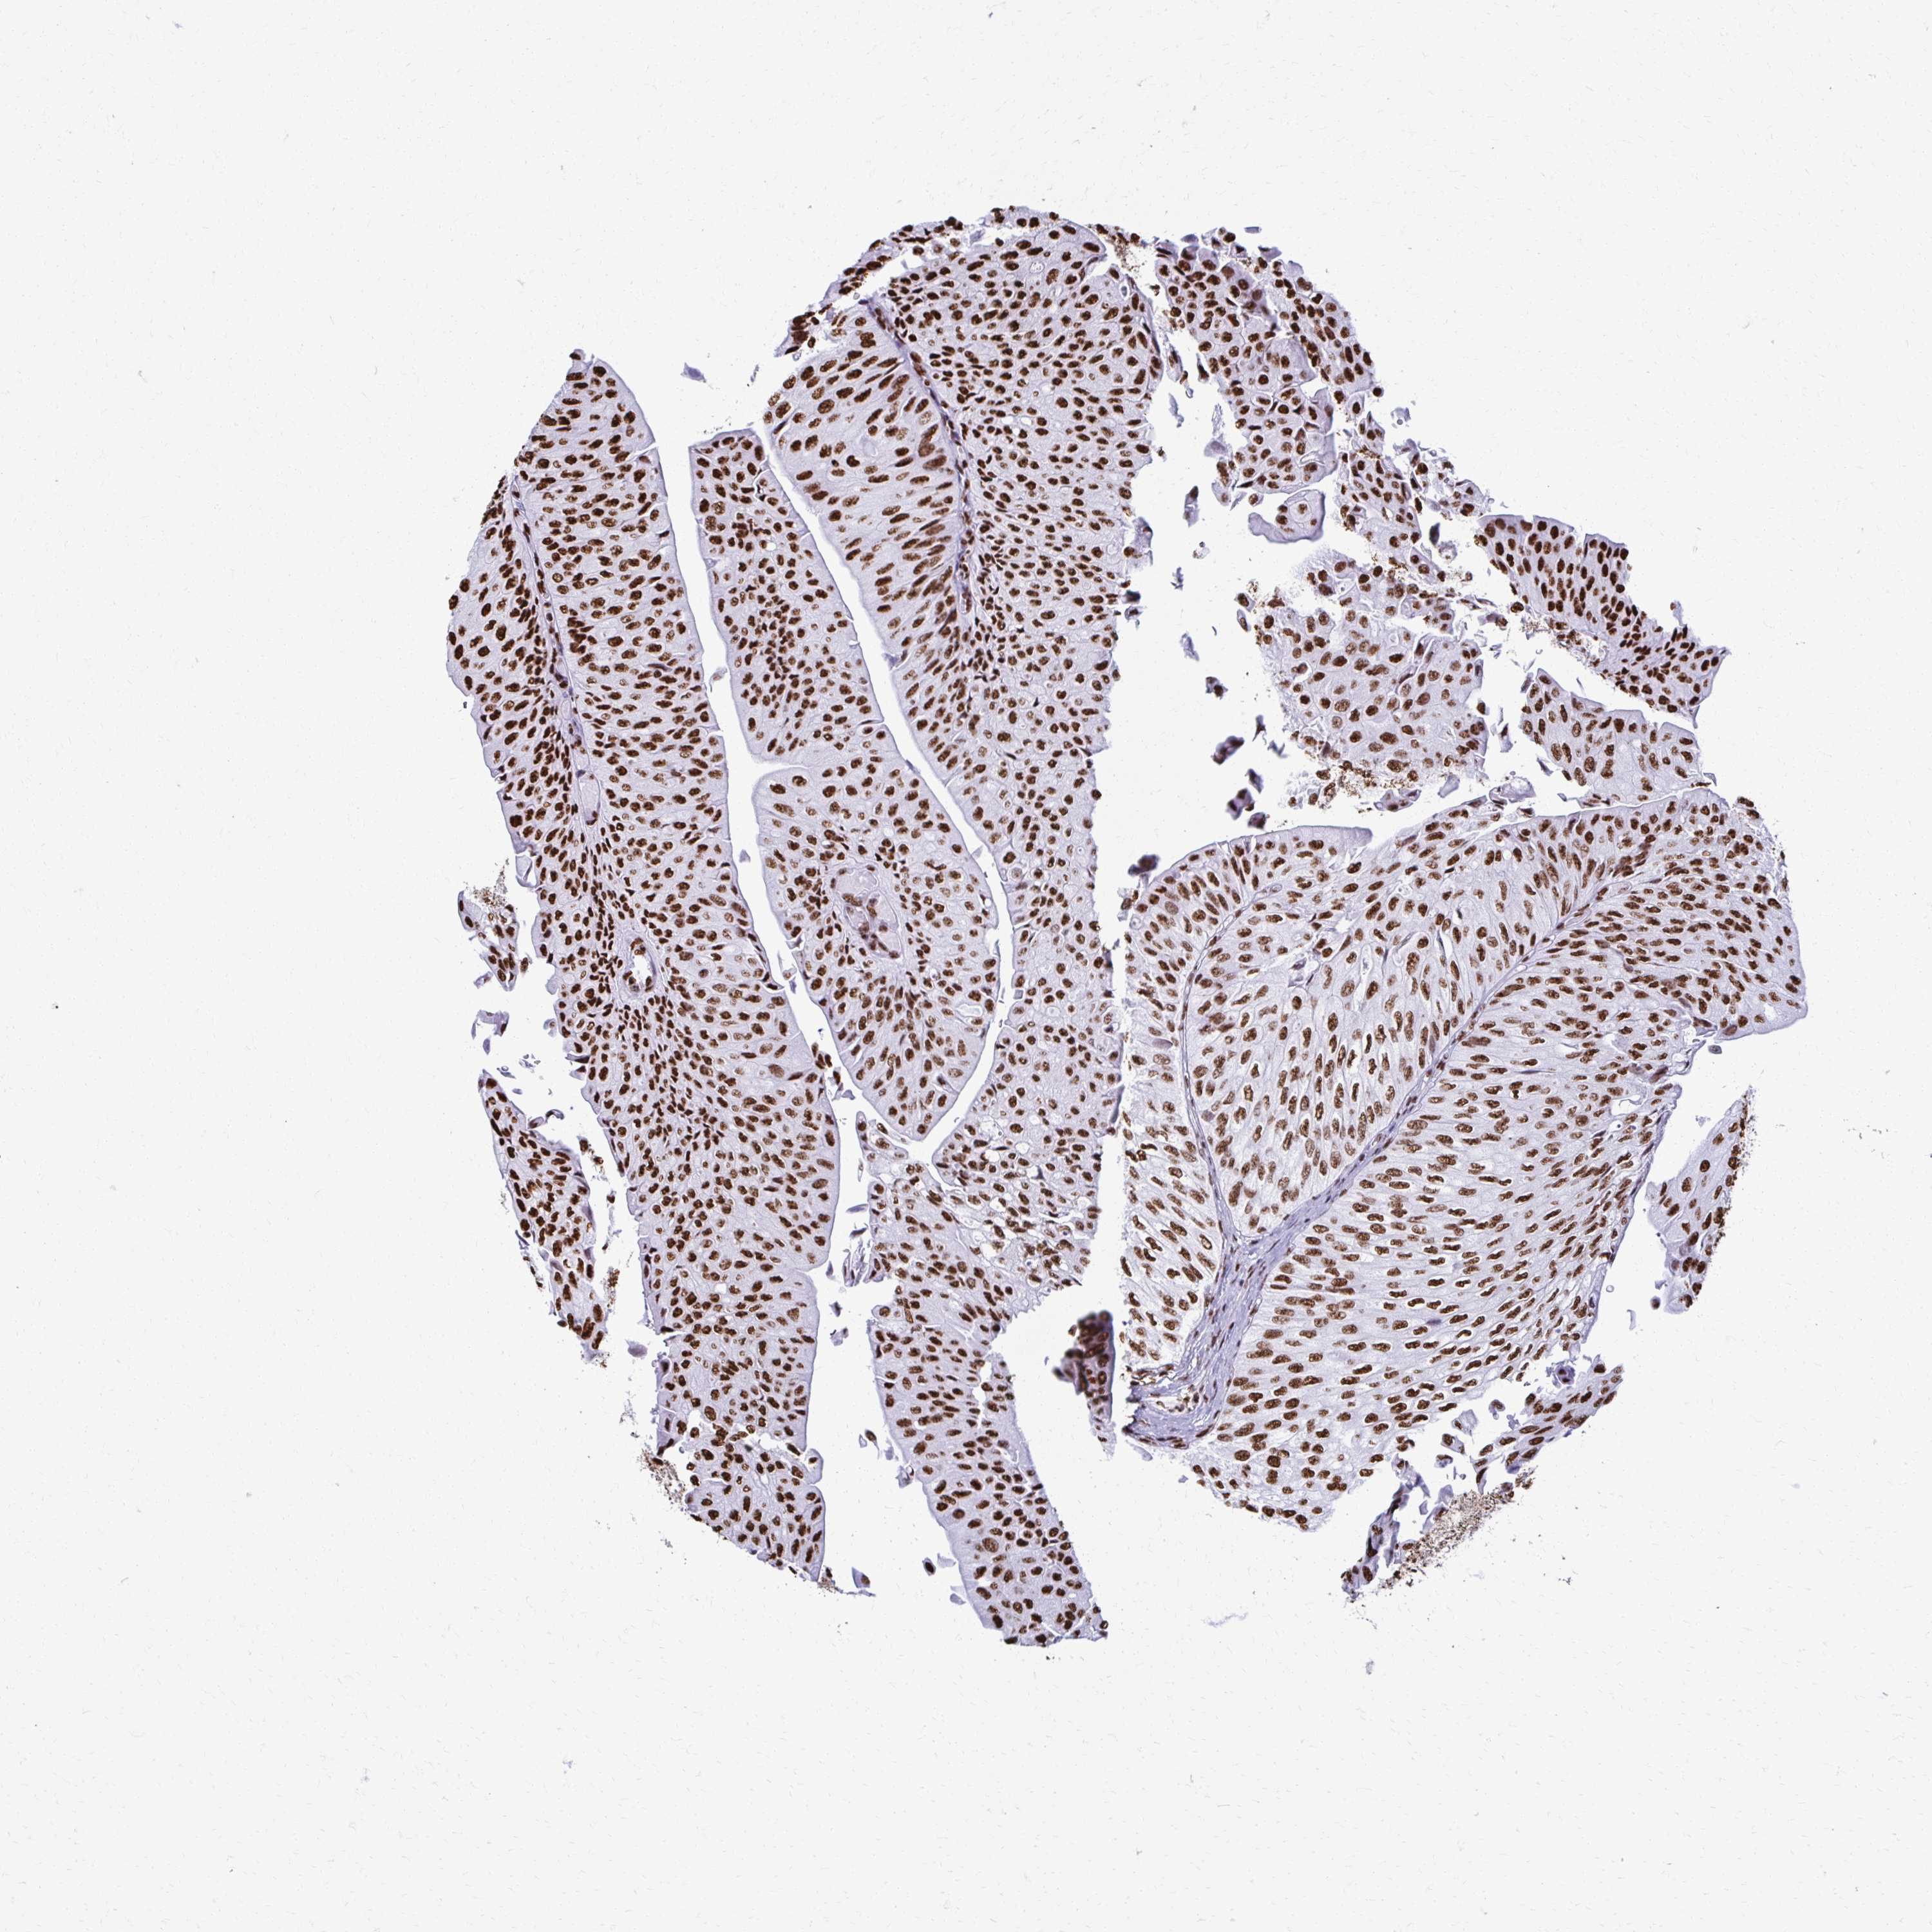

UROTHELIAL CANCER - Protein expressioni

A mouse-over function shows sample information and annotation data. Click on an image to view it in a full screen mode. Samples can be filtered based on level of antibody staining by selecting one or several of the following categories: high, medium, low and not detected. The assay and annotation is described here.

Note that samples used for immunohistochemistry by the Human Protein Atlas do not correspond to samples in the TCGA dataset.

Antibody stainingi

Antibody staining in the annotated cell types in the current human tissue is reported as not detected, low, medium, or high, based on conventional immunohistochemistry profiling in selected tissues. This score is based on the combination of the staining intensity and fraction of stained cells.

Each image is clickable and will lead to virtual microscopy that enables deeper exploration of all samples and also displays staining intensity scores, fraction scores and subcellular localization as well as patient and tissue information for each sample.

Antibody HPA054094

Antibody HPA054559

Antibody CAB022069

Staining

High

Medium

Low

Not detected

Intensity

Strong

Moderate

Weak

Negative

Quantity

>75%

75%-25%

<25%

None

Location

Nuclear

Cytoplasmic/membranous

Cytoplasmic/membranous,nuclear

Urothelial carcinoma, High grade

Urothelial carcinoma, NOS

Urothelial carcinoma, Low grade